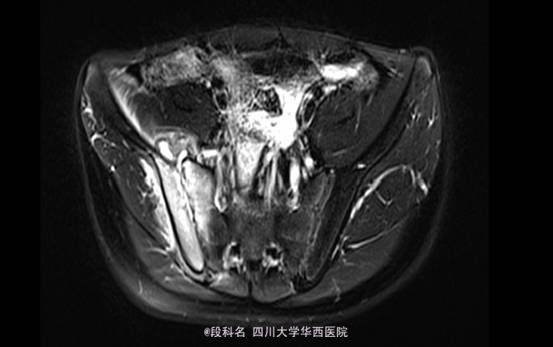

查体:右髋局部无红肿,有压痛,皮温不高,感觉无减退。右侧髋伸屈、外展、内收,因疼痛无法评测。右膝屈曲4级,伸膝3级,踝背伸、跖屈4级 。左侧肌力正常,肌张力正常。右侧直腿抬高试验40°(+),加强实验(+),右侧4字实验(+)。辅助检查:当地医院CT检查示:L4/5椎间盘轻度膨出,L5/S1椎间盘轻度突出,建议MRI检查。我院血常规示:血小板计数 425 10X9/L,白细胞计数 12.26 10^9/L,中性分叶核粒细胞绝对值 8.34 10^9/L。生化示:血沉53.mm/h,C反应蛋白(CRP)42.80mg/L。痰涂片抗酸染色(连续3次):未查见抗酸杆菌。免疫球蛋白A 4050.00 mg/L ↑ 免疫球蛋白M 2240.00 mg/L ↑C-反应蛋白 31.80 mg/L ↑。T细胞亚群正常。CD3细胞亚群 71.40 %CD4细胞亚群 37.00 % CD8细胞亚群 29.80 % CD4/CD8比值 1.24。痰培养示:产酸克雷伯氏菌 混丛,较多。结核抗体检测 阴性 。骨盆MRI示:右侧骶髂关节面骨质见斑片状长T2WI及长T1WI信号,关节间隙模糊、局部狭窄,邻近髂腰肌、梨状肌、臀肌群见斑片状T2WI高信号影。左侧骶髂关节及双侧髋关节未见确切异常。